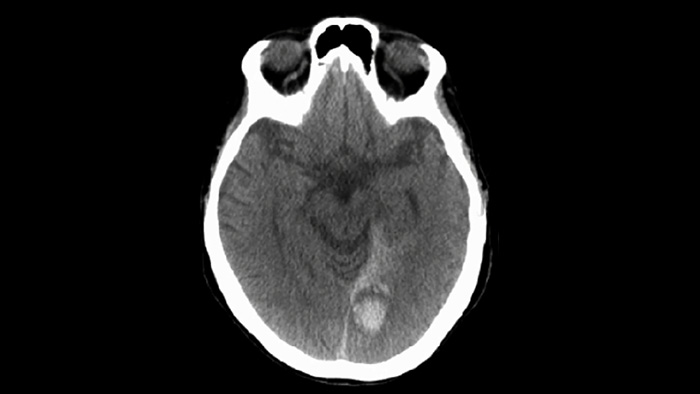

Compruebe si hay hemorragias periprocedimiento

CBCT (similar a TC)

Use la adquisición de imágenes de SmartCT Soft Tissue del paquete Neurovascular para comprobar el éxito del tratamiento e identificar hemorragias.